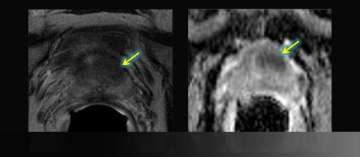

1) Radiation Therapy Follow-Up

Radiation Therapy Follow-Up

• 69 year-old, BPH gradual

• PSA rise 1.6 → 4.8 ng/dl

• Abnormal digital rectal exam → Biopsy: Gleason 5+4=9

• Read More >